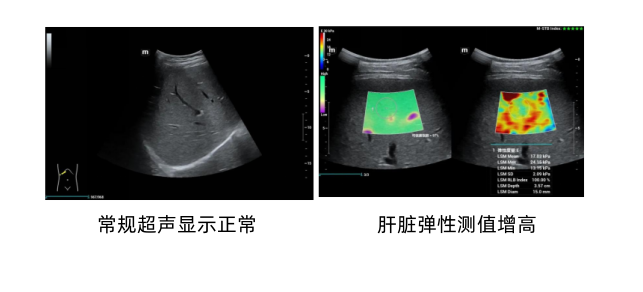

近期,58岁的王先生(化名)因反复肝区隐痛前往古蔺县人民医院就诊。血液检查结果显示其肝功能指标异常,然而常规超声与CT检查却未捕捉到肝脏的明显病变迹象。面对这一“矛盾”情况,超声科团队迅速启动精准诊断方案,为王先生加做肝脏弹性成像检查。令人意外的是,这项检查清晰显示王先生肝脏硬度值超出正常范围,经专业评估肝纤维化分期已达S3期,提示为早期肝硬化。

肝脏弹性成像检查通过超声技术,利用剪切波在肝脏中的传播速度与肝脏组织硬度有关这一特性,将肝脏硬度转化为具体数值,剪切波传播的速度越快,呈现出来的检测值就越高,也就代表着肝纤维化的程度越高。

弹性成像具有无创、快速、准确、易获取、可重复检查等特性,可以定量评分,实现了肝脏纤维化评估的可量化诊断。

如今,弹性成像技术为肝纤维化和肝硬化的评估提供了新的选择。它能直观显示并量化肝脏弹性,实现对肝纤维化和肝硬化的定量评估。该检查方法简单易行,安全可靠,已成为临床诊断和治疗的重要辅助手段。